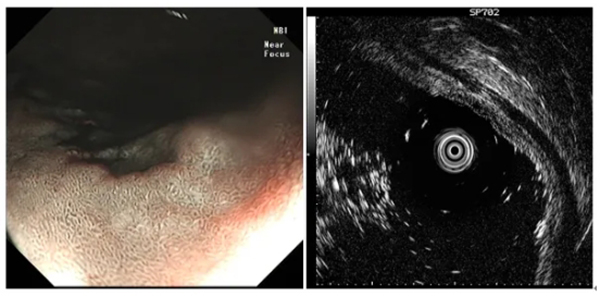

圖示髮(fa)現(xian)消化道早癌并利用(yong)超聲內(nei)鏡判斷(duan)其浸潤深度